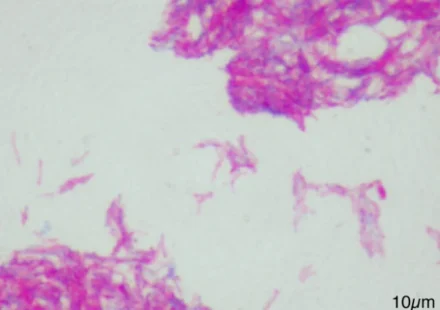

Стресс часто заставляет бактерии образовывать биопленки. Стресс может проявляться в виде физического барьера, ультрафиолета или токсичного вещества, такого как антибиотики. На формирование этих биопленок уходит от нескольких часов до дней, и они могут…